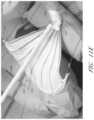

FIG.8A-8B show two views of an embodiment of a coaptation enhancement element comprising afirst surface810 disposed toward a mal-coapting native leaflet, in the instance of a mitral valve, the posterior leaflet and asecond surface820 which may be disposed toward the anterior leaflet. Thesuperior edge840 of the implant may be curved to match the general shape of the annulus or adjoining atrial wall.